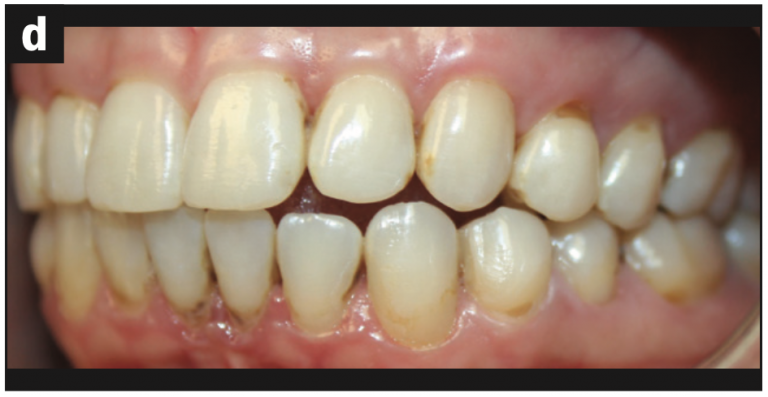

Intraoral images were captured, focusing on three surfaces of each tooth: buccal, occlusal/incisal, and lingual surfaces. The following issues were identified:

- Abfraction with decay (Figures 2a and 2b)

- Abfraction lesions (Figures 2c and 2d)